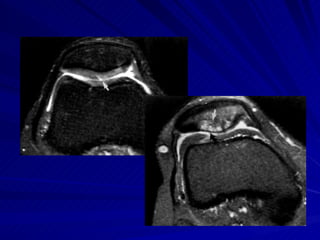

Quadril T2, edema ósseo no ísquio  Alterações degenerativas e rotura do lábio do acetábulo, por artro-ressonância. Paciente: praticante de musculação, com dor no quadril há 10 meses.

Quadril Coronal T1 de quadril e axial stir.